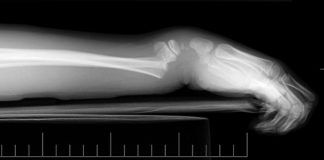

Durant la phase d’autopsie, le médecin légiste a pour principal objectif d’examiner scrupuleusement le corps aussi bien au niveau des parties externes, à la recherche d’ecchymoses ou d’hématomes, qu’au niveau interne, à la recherche de signes de maladie ou de lésions des organes.

Un chapitre sera ensuite consacré aux différents types de blessures pouvant être visibles à l’occasion de l’examen externe. Ces dernières seront classées en fonction de leur degré de gravité.

Enfin, un dernier chapitre abordera la description lésionnelle des blessures pouvant être observées aussi bien à l’examen externe qu’au niveau interne. Cette partie traitera des différentes lésions pouvant être observées en fonction de différents types de mort violente (par armes à feu, armes blanches, asphyxie mécanique, noyade etc.)